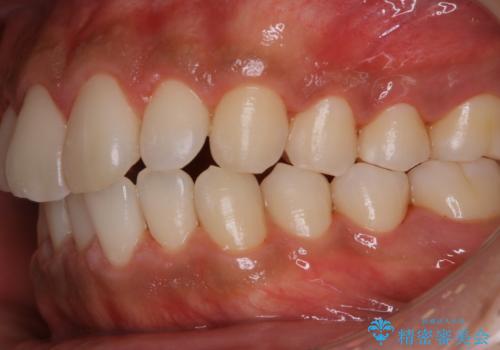

- 特に症状など気になるところはないが、メンテナンスして欲しいとのことでした。染め出しをしてのブラッシング指導とPMTC30分コースを行いました。

磨き残しが多くなると、お口の健康を維持していくのが難しくなってしまいます。お口の健康を守っていくためには、毎日のハミガキを行っていくのが基本です。そのため、なにか症状がなくても定期的に歯科医院で口の健康状態のチェックをすることが大切です。